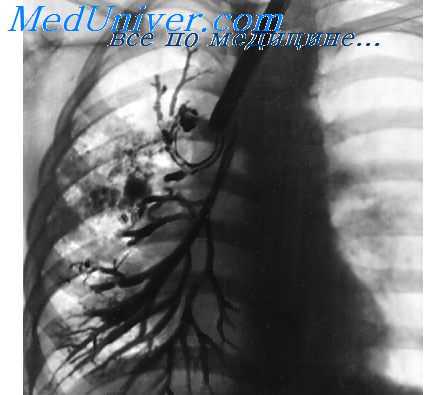

Состояние гемодинамики малого круга кровообращения у больных с ВП с различной степенью тяжести ЭИ оценивали по показатели систолического и диастолического градиента давления легочной артерии (СГДЛА и ДГДЛА соответственно). Полученные результаты представлены в табл. 3.

При выполнении корреляционного анализа показатели гемодинамики малого круга кровообращения показали сильную прямую связь с гематологическими показателями выраженности ЭИ (СГДЛА и ДГДЛА с ЛИИ r=0,6 и 0,7, ГИИ r=0,7 и 0,7 и ЯИИ r=0,5 и 0,5 во всех случаях р<0,05) и обратную связь с величиной ЭЗВД (СГДЛА r=-0,6 и ДГДЛА r=-0,7, р<0,05).

Итак, у большинства больных ВП при III степени ЭИ формируется легочная гипертензия, характеризующаяся повышением сосудистого сопротивления в малом круге кровообращения на фоне снижения эффективности местных механизмов регуляции циркуляторного гомеостаза. Результирующим клиническим проявлением данной патологии является выраженное нарушение функции внешнего дыхания по рестриктивному типу.